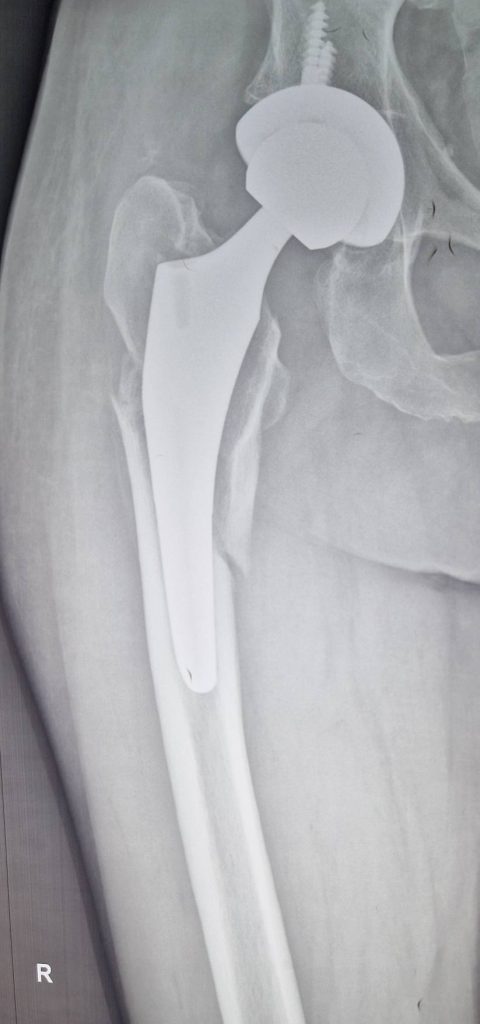

Ревізійне ендопротезування, при перипротезних переломах, особливо тип В2, потребує заміни ніжки протеза, як правило на ревізійну, і стабільного остеосинтеза відламків проксимального відділу стегнової кістки з заміщенням дефектів кістки трансплататом.

Клінічний приклад ревізійного ендопротезування при перипротезному переломі стегнової кістки представлено на рентгенограмах.

Ревізійне ендопротезування, при перипротезних переломах, особливо тип В2, потребує заміни ніжки протеза, як правило на ревізійну, і стабільного остеосинтеза відламків проксимального відділу стегнової кістки з заміщенням дефектів кістки трансплататом. Клінічний приклад ревізійного ендопротезування при перипротезному переломі стегнової кістки представлено на рентгенограмах.